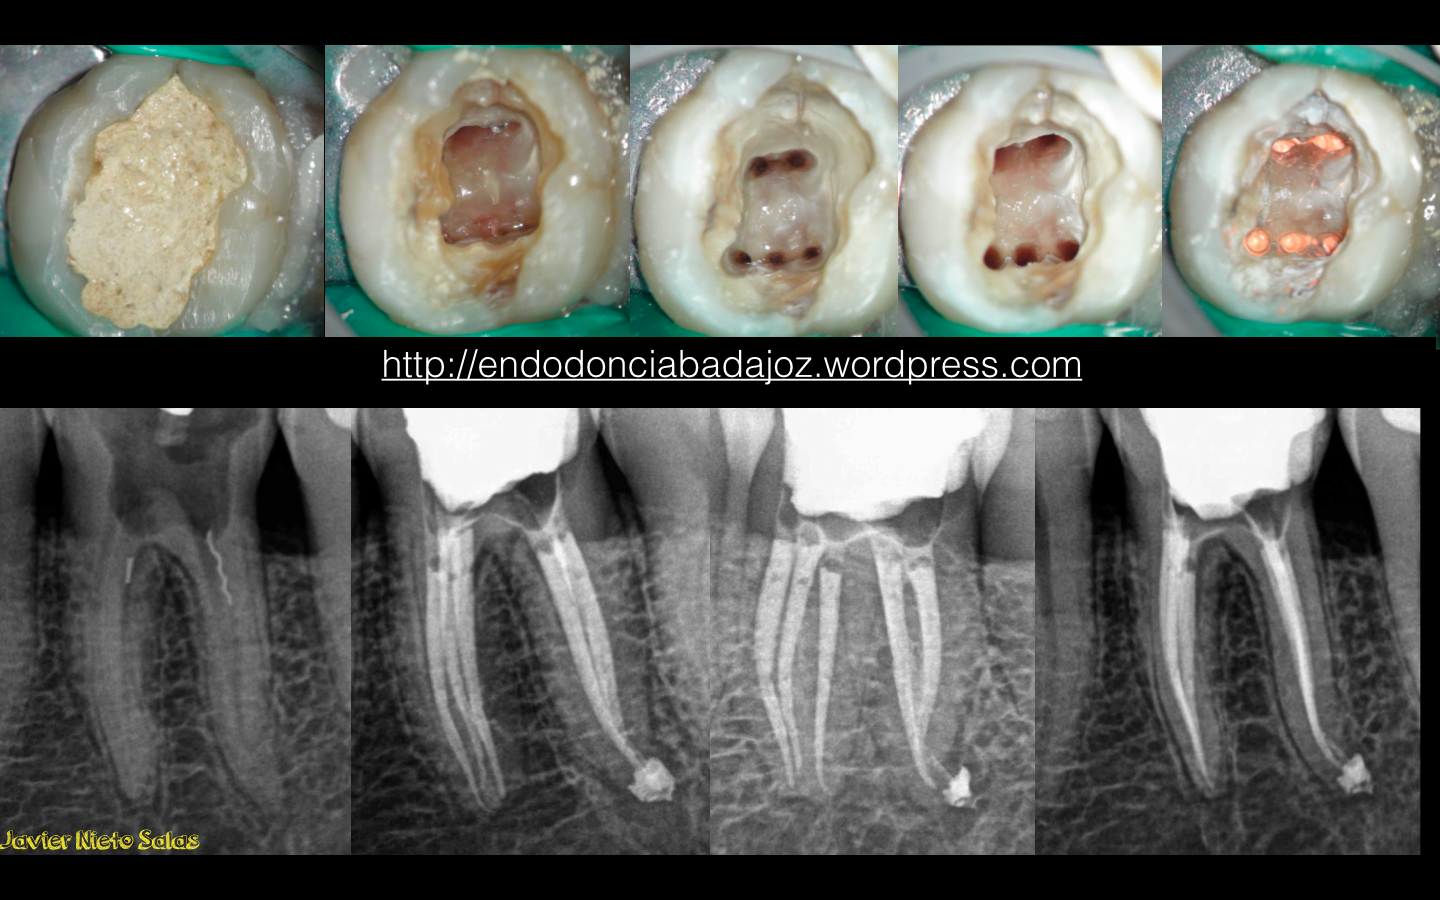

En la secuencia fotográfica y radiográfica del caso, podemos ver que en el diagnóstico inicial, vemos un par de limas separadas, y una gran apertura con una línea de  fisura distal que no sabemos su alcance.  Siendo, estas dos situaciones las que me van a determinar el pronóstico del caso:

a) si la línea de fisura la podemos eliminar, con lo que eliminaríamos una entrada de bacterias en los conductos

b) si las limas separadas no nos bloquean el sistemas de conductos  y podemos eliminar todo el tejido necrótico y bacteriano del mismo.

Instrumentamos los conductos con el Sistema Mtwo, con una conicidad de 25.6%,  y la técnica de obturación que usamos fue una Condensación vertical con ola continua de Buchanan modificada. Hacemos un sellado coronal con composite fluido.

Se eliminó la linea de fisura distal con las fresas de tugsteno Munce. Siendo esta su secuencia fotográfica: